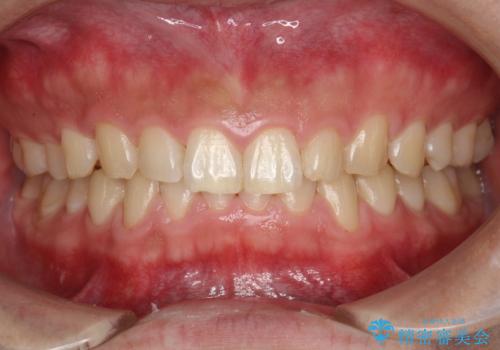

60分のPMTCで歯の黄ばみをきれいに除去

- 年末年始と忙しく、なかなか歯のケアがしっかりできなかった事と着色も気になるとのことで来院されました。PMTC60分コースを行いました。